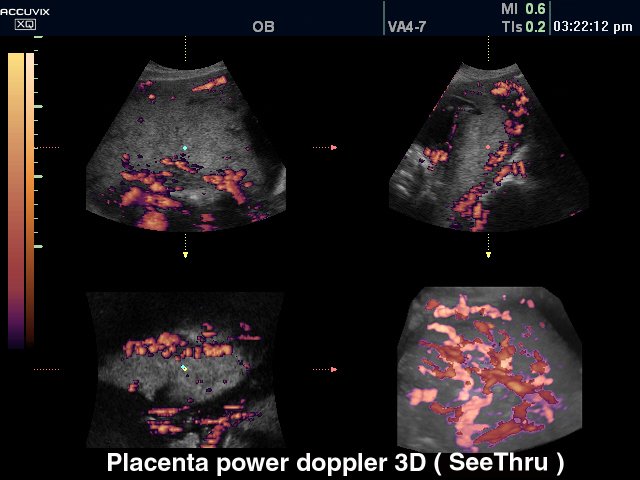

Placenta, power doppler, 3D

Placenta, power doppler, 3D (echogramm №318)

[RU] Ultrasound image №318: Placenta in power doppler and 3D mode.

Echogramm was received by ultrasound scanner Accuvix-XQ (out of production).